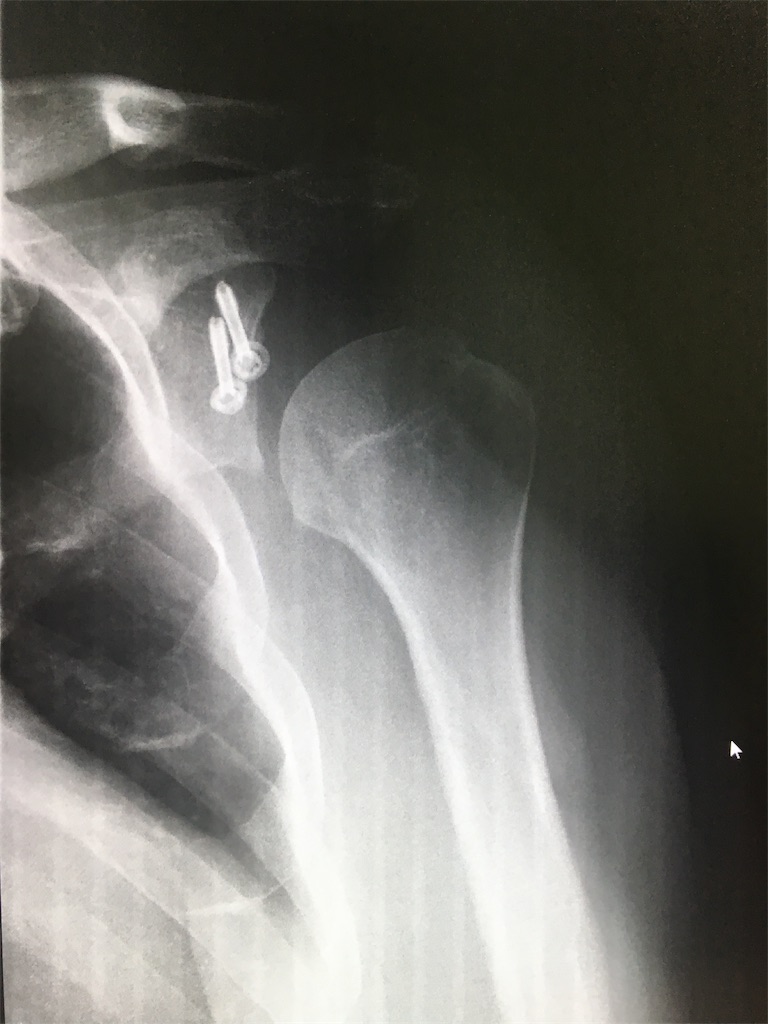

肩 脱臼 手術 ブログ 肩の脱臼は手術した方が良い?癖で痛みが出るのは完治してい 反復性肩関節脱臼の発症から治療、手術、完治までのブログ; おわりに 本記事は「費用編肩の亜脱臼に困って手術した話」について書きました。 まとめると、亜脱臼の手術から完治には 約231,118円(交通費含まず) の費用がかかりました。 私の場合は個人で入っていた傷害保険が適用されてので、実質的には13肩鎖関節脱臼と比べるとレントゲンだけでは診断しにくい場合が多く、見逃されやすい脱臼です。 多くの場合は超音波検査やCT検査も行い診断します。 《治療》 前方脱臼は手術を行わないで鎖骨骨折の際に使用する鎖骨バンドで固定する場合が多いです。 後方脱臼や改善しない前方脱臼は手術を行う場合が多く、針金や強靭な糸を使った手術を行うことがあります

ということでもし、脱臼手術を受けて活躍されているスポーツ選手がいたら教えてください。 メンバーの方なら、ご自分のブログでお話されても結構です。 自分のほうはトラックバックしますんで。 バブの反復性肩関節前方脱臼のhp へ戻る肩の痛みでお困りの方は一度ご相談ください。 主に下記の疾患に対して保存的加療(注射・リハビリなど)、手術加療(関節鏡・直視下)を行なっております。 ・腱板断裂 ・反復性肩関節脱臼 ・変形性肩関節症右肩鎖関節脱臼・・・入院・手術編 (28) カテゴリ: ケガ 前回の伊那サーキットでの転倒事故から、皆様にご心配をお掛けしております コメントを頂いた方々、メールをくれた皆様、本当にありがとうございます。 一応、その後の状況を報告させて頂きますね! 27日(土)の転倒した当日は、夜間に救急センターにて右肩を固定されて 前回のブログ 内容の処置の